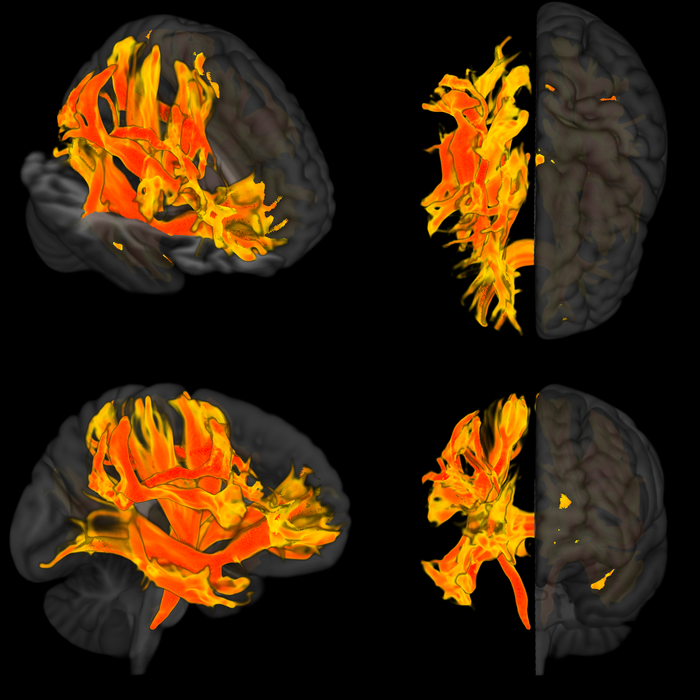

Ερευνητές εντόπισαν για πρώτη φορά συγκεκριμένες περιοχές του εγκεφάλου που έχουν υποστεί βλάβη από την υψηλή αρτηριακή πίεση και μπορεί να συμβάλουν στη μείωση των νοητικών διεργασιών και στην ανάπτυξη άνοιας.

Οι ερευνητές εντόπισαν ότι οι αλλαγές σε εννιά μέρη του εγκεφάλου σχετίζονται με την υψηλότερη αρτηριακή πίεση και τη χειρότερη γνωστική λειτουργία. Οι αλλαγές σε αυτές τις περιοχές περιελάμβαναν μειώσεις στον όγκο του εγκεφάλου και στην έκταση της επιφάνειας του εγκεφαλικού φλοιού, αλλαγές στις συνδέσεις μεταξύ διαφορετικών τμημάτων του εγκεφάλου και αλλαγές στην εγκεφαλική δραστηριότητα.

«Χρησιμοποιώντας αυτό τον συνδυασμό προσεγγίσεων απεικόνισης, γενετικής και παρατήρησης εντοπίσαμε συγκεκριμένα μέρη του εγκεφάλου που επηρεάζονται από την αύξηση της αρτηριακής πίεσης, συμπεριλαμβανομένων των περιοχών που ονομάζονται κέλυφος φακοειδούς πυρήνα και συγκεκριμένων περιοχών λευκής ουσίας. Πιστεύαμε ότι αυτές μπορεί να είναι οι περιοχές, όπου η υψηλή αρτηριακή πίεση επηρεάζει τη γνωστική λειτουργία, όπως η απώλεια μνήμης, οι δεξιότητες σκέψης και η άνοια. Όταν ελέγξαμε τα ευρήματά μας μελετώντας μια ομάδα ασθενών στην Ιταλία που είχαν υψηλή αρτηριακή πίεση, διαπιστώσαμε ότι τα μέρη του εγκεφάλου που είχαμε εντοπίσει είχαν όντως επηρεαστεί», δηλώνει ο Τόμας Γκούζικ, καθηγητής Καρδιαγγειακής Ιατρικής στο Πανεπιστήμιο του Εδιμβούργου και στο Ιατρικό Κολέγιο του Γιαγκελόνιου Πανεπιστημίου της Κρακοβίας, ο οποίος ηγήθηκε της έρευνας.